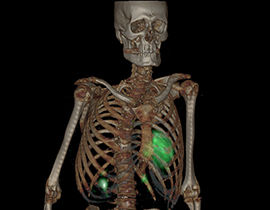

Erweiterte Visualisierung für CT